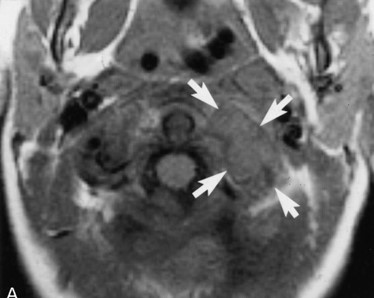

• T1WI、T2WI、Gd-T1WI

• T2WI

• T1WI

• Gd-T1WI